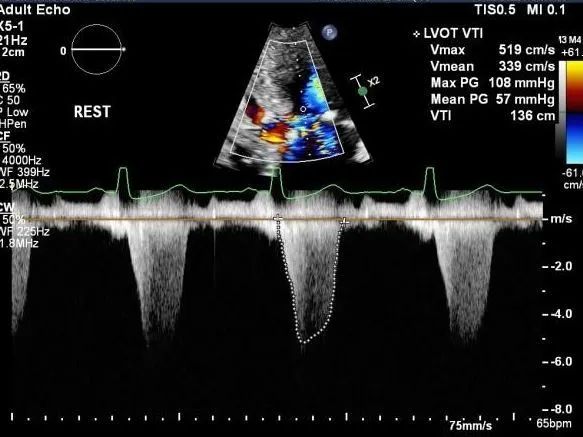

患者是一位70岁的女性, 超声提示,患者室间隔最大厚度为20.8mm,静息状态下左室流出道重度梗阻,压差为118mmHg。负荷状态下122mmHg。

术后左室流出道压差

病例2

患者是一位58岁的女性。超声提示患者室间隔最大厚度为26.3mm,静息状态左室流出道压差为118mmHg,负荷状态下为233mmHg。

病例3

患者为一名40岁的女性。超声提示患者室间隔最大厚度为31.3mm,静息压差为102mmHg,负荷状态下为146mmHg。二尖瓣呈SAM征伴有少量反流。